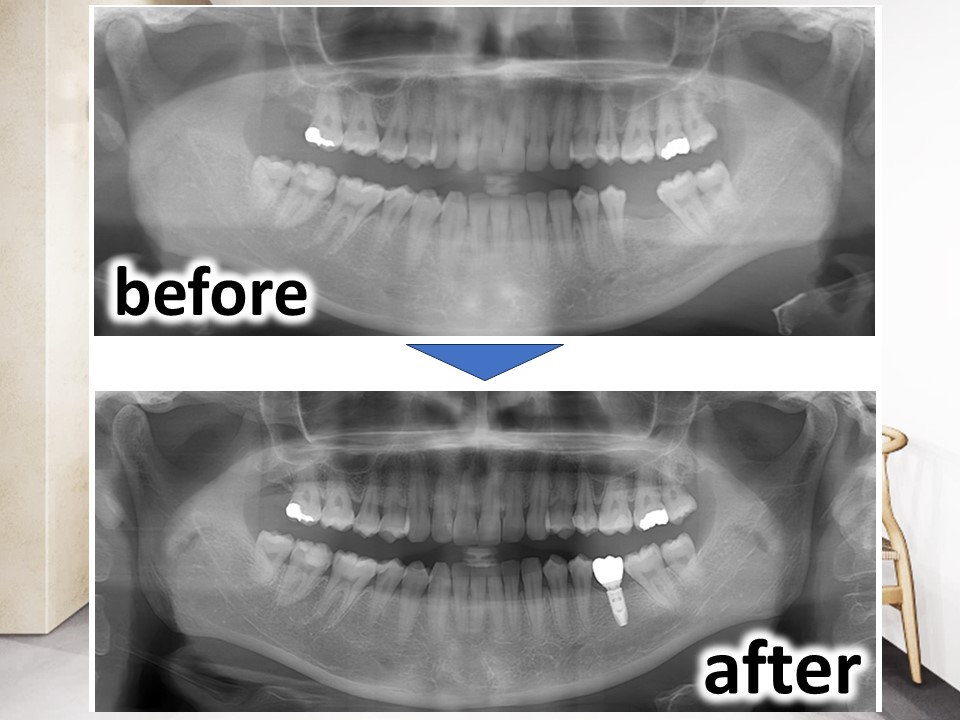

今回は、左下の奥歯の欠損に対して、インプラント治療を行った症例について供覧いたします。

診断:左下6欠損、インプラントを埋入するには残存骨が不足している

治療:人工骨を用いた骨造成(GBR)、インプラント治療

他院では骨が少ないため、同部のインプラント治療は難しいといわれ、何とかインプラント治療ができないかということで当院を受診されました。

インプラント治療により、またしっかりと奥歯で咬めるようになったと、患者さまには大変満足いただいております。